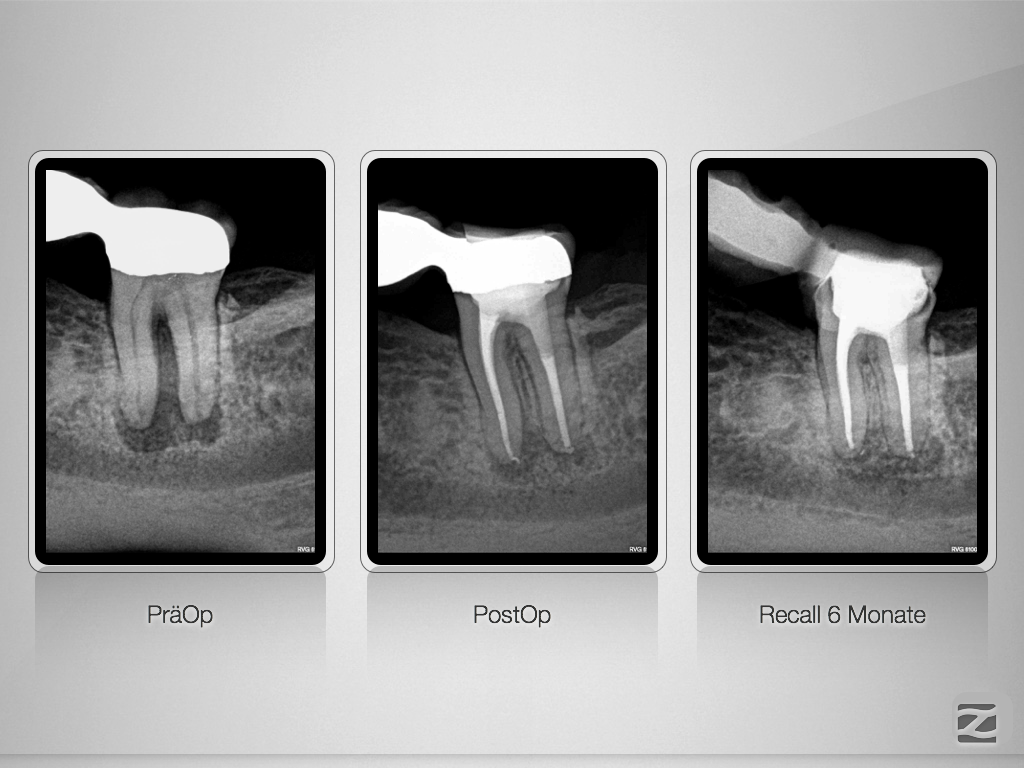

37D.004

Erstaunlich schnell